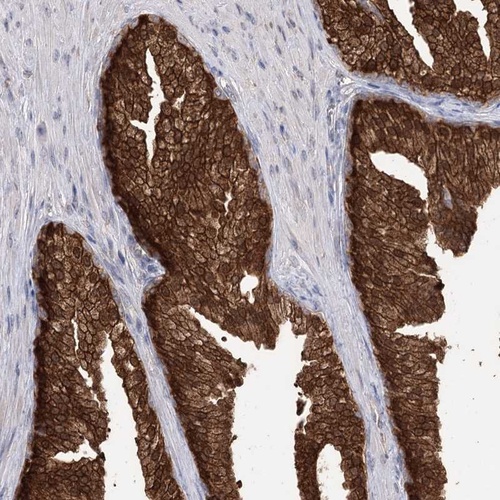

Immunohistochemical staining of human prostate shows strong cytoplasmic and nuclear positivity in glandular cells.